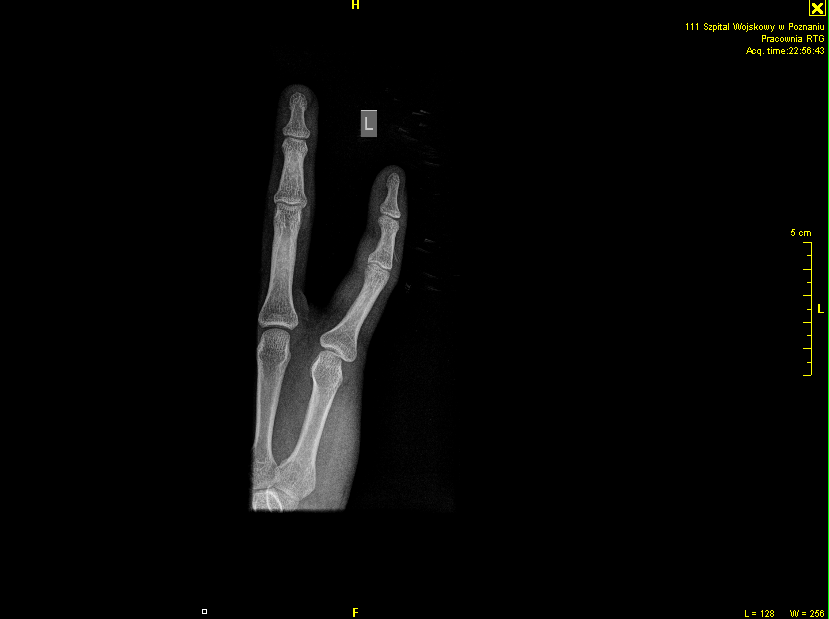

so I got a situation with my small finger during my basketball session yesterday in the afternoon. at first i thought that it just hurts and I will be fine soon, no need to go to the doctor. So i took few painkillers, got some ice to my finger and sit down but after some minutes of gaming and constantly pushing Shift it's started to be annoying SO i thought it might be broken but after I went to the hospital (soz team kresti ^^) it turned out to be just twisted(?) ;d